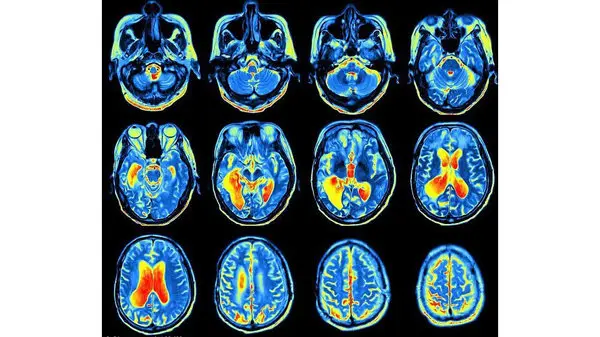

آژانس تحقیقات دفاعی پیشرفته ارتش آمریکا برای نخستین بار در حال آزمایش یک ایمپلنت Implant مغزی را روی انسان است که می‌تواند رفتار و حرکات یک فرد را تغییر دهد.

به گزارش دیلی میل، این تراشه‌های کنترل‌کننده مغز، پالس‌های الکترونیکی را منتشر می‌کنند که طی فرآیندی به نام "تحریک مغزی عمیق"، عملکرد شیمیایی مغز را تغییر می‌دهد.

تراشه‌های کنترل ذهن که توسط ارتش آمریکا تولید می‌شود، پس از آزمایش روی انسان برای اولین بار، می‌تواند برای کنترل رفتار و حرکات مورد استفاده قرار گیرد.تحریک مغزی عمیق با کاشت سیم‌های ظریفی در مغز که الکترودهایی در سرشان قرار دار، انجام می‌شود.

این سیم‌ها دنباله‌هایی دارند که زیر پوست تا پشت گوش و پایین گردن ادامه پیدا می‌کنند.الکترودها، شوکی با فرکانس بالا به یک ناحیه مورد نظر مغز وارد می‌کنند.

این تحریک، برخی از سیگنال‌های الکتریکی را در مغز تغییر می‌دهند تا رفتار و حرکات را عوض کنند.تحریک مغزی عمیق برای درمان اختلالات حرکتی مانند پارکینسون مورد استفاده قرار گرفته اما تاکنون موفقیت کمی در درمان اختلالات روحی داشته‌ است.